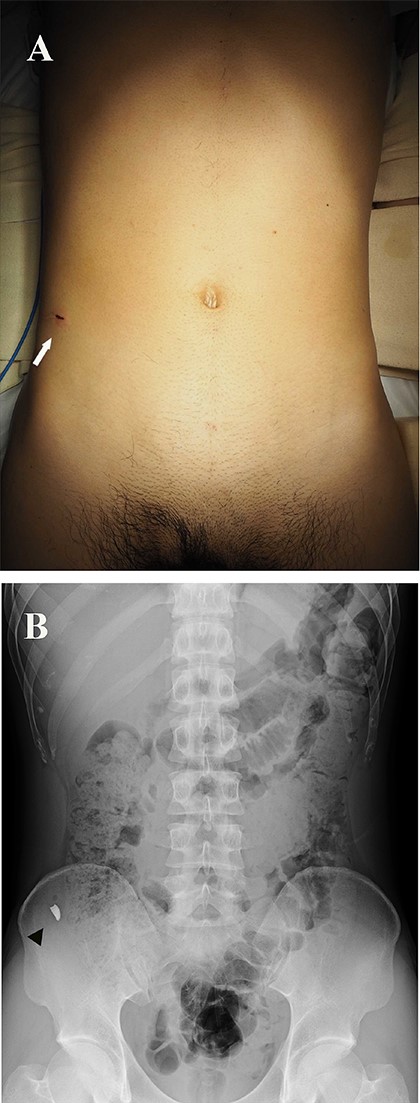

A 27-year-old man working in a forging factory presented to our hospital with acute abdominal pain. He reported that, 3 hours before presentation, a metal fragment came flying from the operating power hammer, which molded molten metal into the desired shape by striking it. Although he was wearing protective clothing, the fragment penetrated through it and caused sharp pain. Physical examination revealed a 1 cm wound, resembling a stab wound above the right iliac crest (Fig. 1A). The patient experienced localized abdominal pain around the wound; however, there were no signs of peritoneal irritation. His vital signs were stable and laboratory data showed no abnormalities except for a slightly increased C-reactive protein level of 0.91 mg/dL (reference range, 0–0.14). A spine abdominal radiograph showed a 1 cm-sized radiopaque object in the lower right abdomen (Fig. 1B). An abdominal computed tomography revealed a radiopaque object near the peritoneum; however, its exact location being extraperitoneal or intraperitoneal could not be determined (Fig. 2A and B). The abdominal cavity did not have free air or fluid retention. The patient was diagnosed to have a foreign body near the peritoneum and surgical removal was planned. The operation was performed using single-incision plus one-port laparoscopic surgery (SILS plus one). A 1.5 cm longitudinal incision was made at the umbilicus to access the abdominal cavity, after which the wound retractor (Smart Retractor XS; TOP Corp., Tokyo, Japan) was inserted. It was mounted to a single-port access device (Free Access; TOP Corp., Tokyo, Japan). Subsequently a 5-mm trocar was placed just above the pubic symphysis. Laparoscopic inspection following pneumoperitoneum revealed no damage to the peritoneum or internal organs (Fig. 3A). Although we assumed the foreign body was located in the abdominal wall, laparoscopic inspection could not confirm its position. Real-time fluoroscopy was used to locate the fragment. The nearest peritoneum was incised and the abdominal muscle was dissected until the foreign body was observed (Fig. 3B). It was found embedded in the transversus abdominis muscle (Fig. 3C) and was safely removed using forceps (Fig. 3D). The object was 1.5 cm long and sharp at both ends (Fig. 4). The patient was discharged from our hospital after a good postoperative course.

(A) Photograph showing a 1 cm entrance wound, similar in appearance to a stab wound above the right iliac crest (arrow). (B) Spinal abdominal radiograph showing a 1 cm-sized radiopaque object in the lower right abdomen (arrow head).